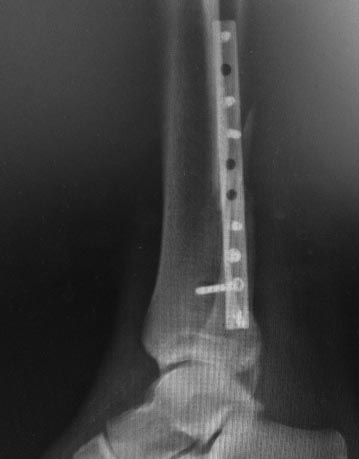

Обратился пациент 37 лет,офисный работник, без вредных привычек. 2,5

месяца назад травма голеностопного сустава. Выполнен остеосинтез. Ходил

без нагрузки на ногу в ортезе. К нам пациент обратился спустя 2,5 месяца

после операции. Местно- область голеностопного сустава умеренно отечна.

Послеоперационный рубец по боковой поверхности малоберцовой

кости без признаков воспаления.

Интересует мнения об особенностях реостесинтеза

Что делать c переломом после восстановления длинны и положения

дистального отдела малоберцовой кости (насколько травматично обращались

с осколками при первой операции неизвестно)

-делать ли костную пластику?(не вижу признаков сращения на последнем

контроле)

-зафиксировать ли достаточно большой фрагмент по задней поверхности

малоберцовой кости?